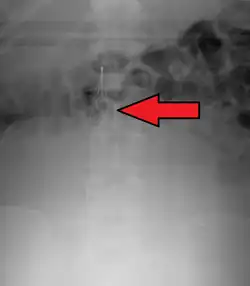

Abdominal radiograph shows that one of the legs (arrows) of the IVC filter is pointed away from the expected IVC lumen.

Axial CT image confirms that one of the legs (arrow) of the IVC filter has migrated out of the IVC wall into an adjacent tissue.